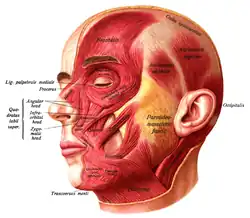

The discipline of anatomy is divided into macroscopic and microscopic parts. Macroscopic anatomy, or gross anatomy, is the examination of an animal's body parts using unaided eyesight. Gross anatomy also includes the branch of superficial anatomy. Microscopic anatomy involves the use of optical instruments in the study of the tissues of various structures, known as histology, and also in the study of cells. (Full article...)

Gray's Anatomy is a reference book of human anatomy written by Henry Gray, illustrated by Henry Vandyke Carter and first published in London in 1858. It has had multiple revised editions and the current edition, the 42nd (October 2020), remains a standard reference, often considered "the doctors' bible".

Earlier editions were called Anatomy: Descriptive and Surgical, Anatomy of the Human Body and Gray's Anatomy: Descriptive and Applied, but the book's name is commonly shortened to, and later editions are titled, Gray's Anatomy. The book is widely regarded as an extremely influential work on the subject. (Full article...)